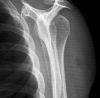

Schulter Y-Aufnahme a.-p. (lateral)

Technik

• FDA: 1,15 m

• Ausgangsformat: 24/30 hoch

• mit Raster

Indikation

Fraktur, Luxation, Osteosynthesematerial

Lagerung

sitzend/ stehend aufrecht am Rasterwandstativ

Hand der aufzunehmenden Seite ruht/liegt auf Bauchmitte

zu untersuchende Seite um ca. 45° anheben - Scapula-Ränder überlagern sich

Zentralstrahl

Querstrahl: ergibt sich - oberes Licht 2 QF über Schulter-Haut-Grenze

Längsstrahl: ca. Mitte Oberarmkopf

Anmerkung

Aufnahme auch im Liegen und im p.-a. Strahlengang möglich

Qualitätskriterien

Scapula stellt sich Y-förmig ohne Rippenüberlagerung dar. Humerus und Scapula überdecken sich. Gelenkpfanne befindet sich im Schnittpunkt der 3 Schenkel vom Y.